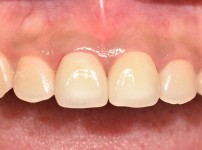

8

BEFORE

AFTER

클릭 해주세요.

Smilefit 심미보철

심미보철